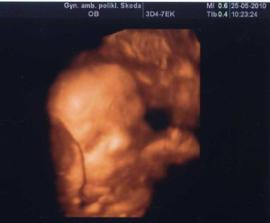

14.01.2010 15t + 4 máme 8,36cm a vše je v pořádku,už jsou nám vidět i kořínky na zoubky,prý vypadáme jak krokodýl 🙂) za týden výsledky krevních testů,snad bude vše ok...( o týden později - výsledky dopadli výborně a nemusíme na odběr plodové vody)